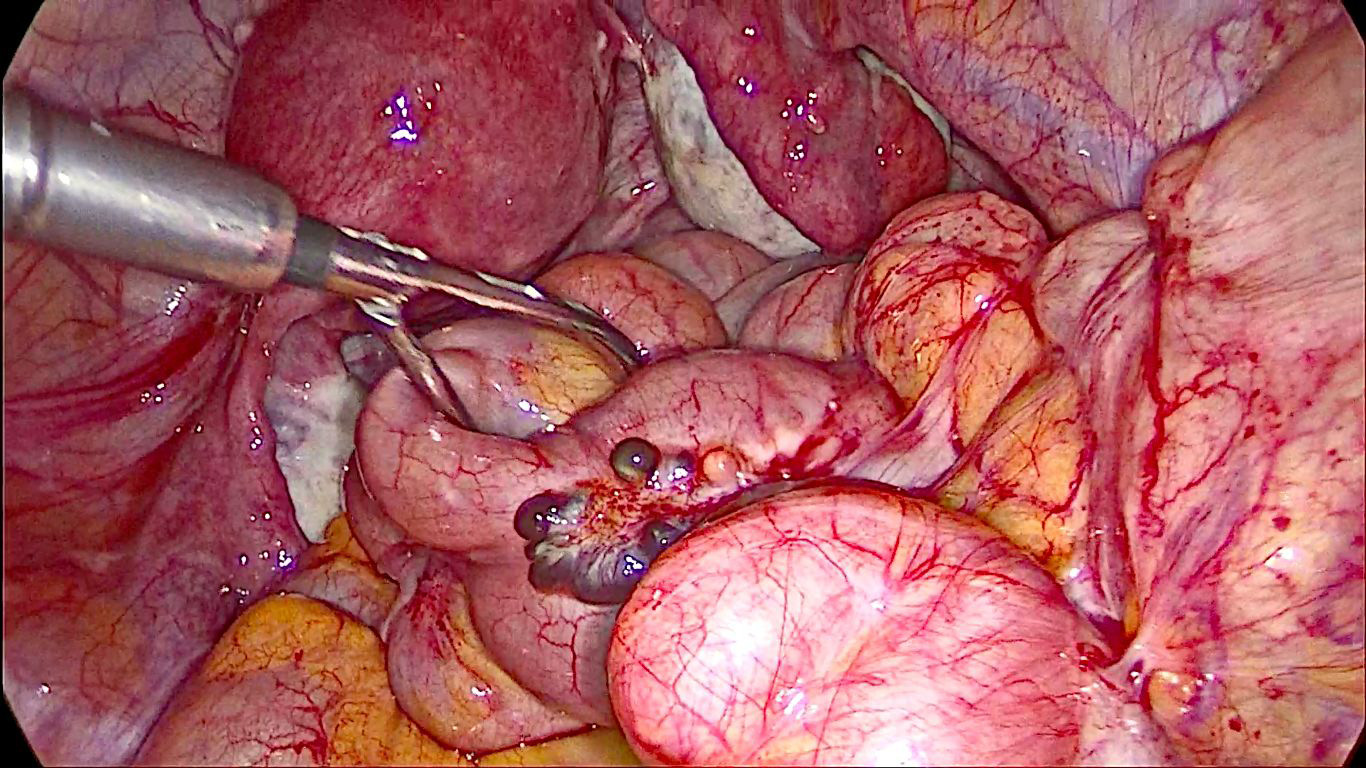

Больной выполнена лапароскопически ассистированная правосторонняя гемиколэктомия. Под эндотрахеальным наркозом выше пупка открытым доступом по Hassen установлен 12-миллиметровый троакар с видеокамерой. Инсуфляция. Рабочие троакары установлены в типичных точках. В брюшной полости выпота нет. В правой подвздошной ямке, в куполе слепой кишки определяется опухолевидное образование, суживающее просвет кишки; белесоватый булавовидно утолщенный в верхней трети червеобразный отросток; по ходу подвздошной кишки на расстоянии 20 см от баугиневой заслонки на серозной оболочке образование по типу «грозди винограда», представленное синюшно-багровыми тонкостенными кистами диаметром от 0,5 до 3 см, содержимое — гемолизированная кровь. Между кистами определяются тяжи белесоватой ткани (рис. 2, 3).

Рис. 2. Лапароскопия — ревизия органов малого таза и брюшной полости / Fig. 2. Laparoscopy — revision of the pelvic organs and abdominal cavity

Рис. 3. Лапароскопия — образование подвздошной кишки / Fig. 3. Laparoscopy — formation of the ileum

Стенка кишки деформирована обнаруженным образованием, просвет ее сужен (опухоль? внутриорганное метастазирование?); также на расстоянии 30 см от баугиневой заслонки располагается дивертикул Меккеля. В печени, желчном пузыре, желудке, сальнике, толстой и тонкой кишках патологии не выявлено. Тело матки нормальных размеров, «мраморной» окраски, в дне матки миоматозный узел диаметром 5 мм, придатки с обеих сторон не изменены. С учетом наличия опухоли в слепой и подвздошной кишках, а также отсутствия распространения процесса принято решение выполнить правостороннюю гемиколэктомию. Медиальным доступом мобилизованы правая половина толстой кишки и 40 см терминального отдела подвздошной кишки, верхнебрызжеечная артерия и вена клипированы, пересечены у основания, a. и v. colica media, a. и v. colica dextra лигированы, пересечены у основания. Срединная мини-лапаротомия. Проксимально отсечена кишка в 40 см от илеоцекального угла, дистально — на уровне середины восходящей ободочной кишки при помощи линейного сшивающего аппарата. Сформирован илеотрансверзоанастомоз «бок в бок» двухрядным ручным швом.